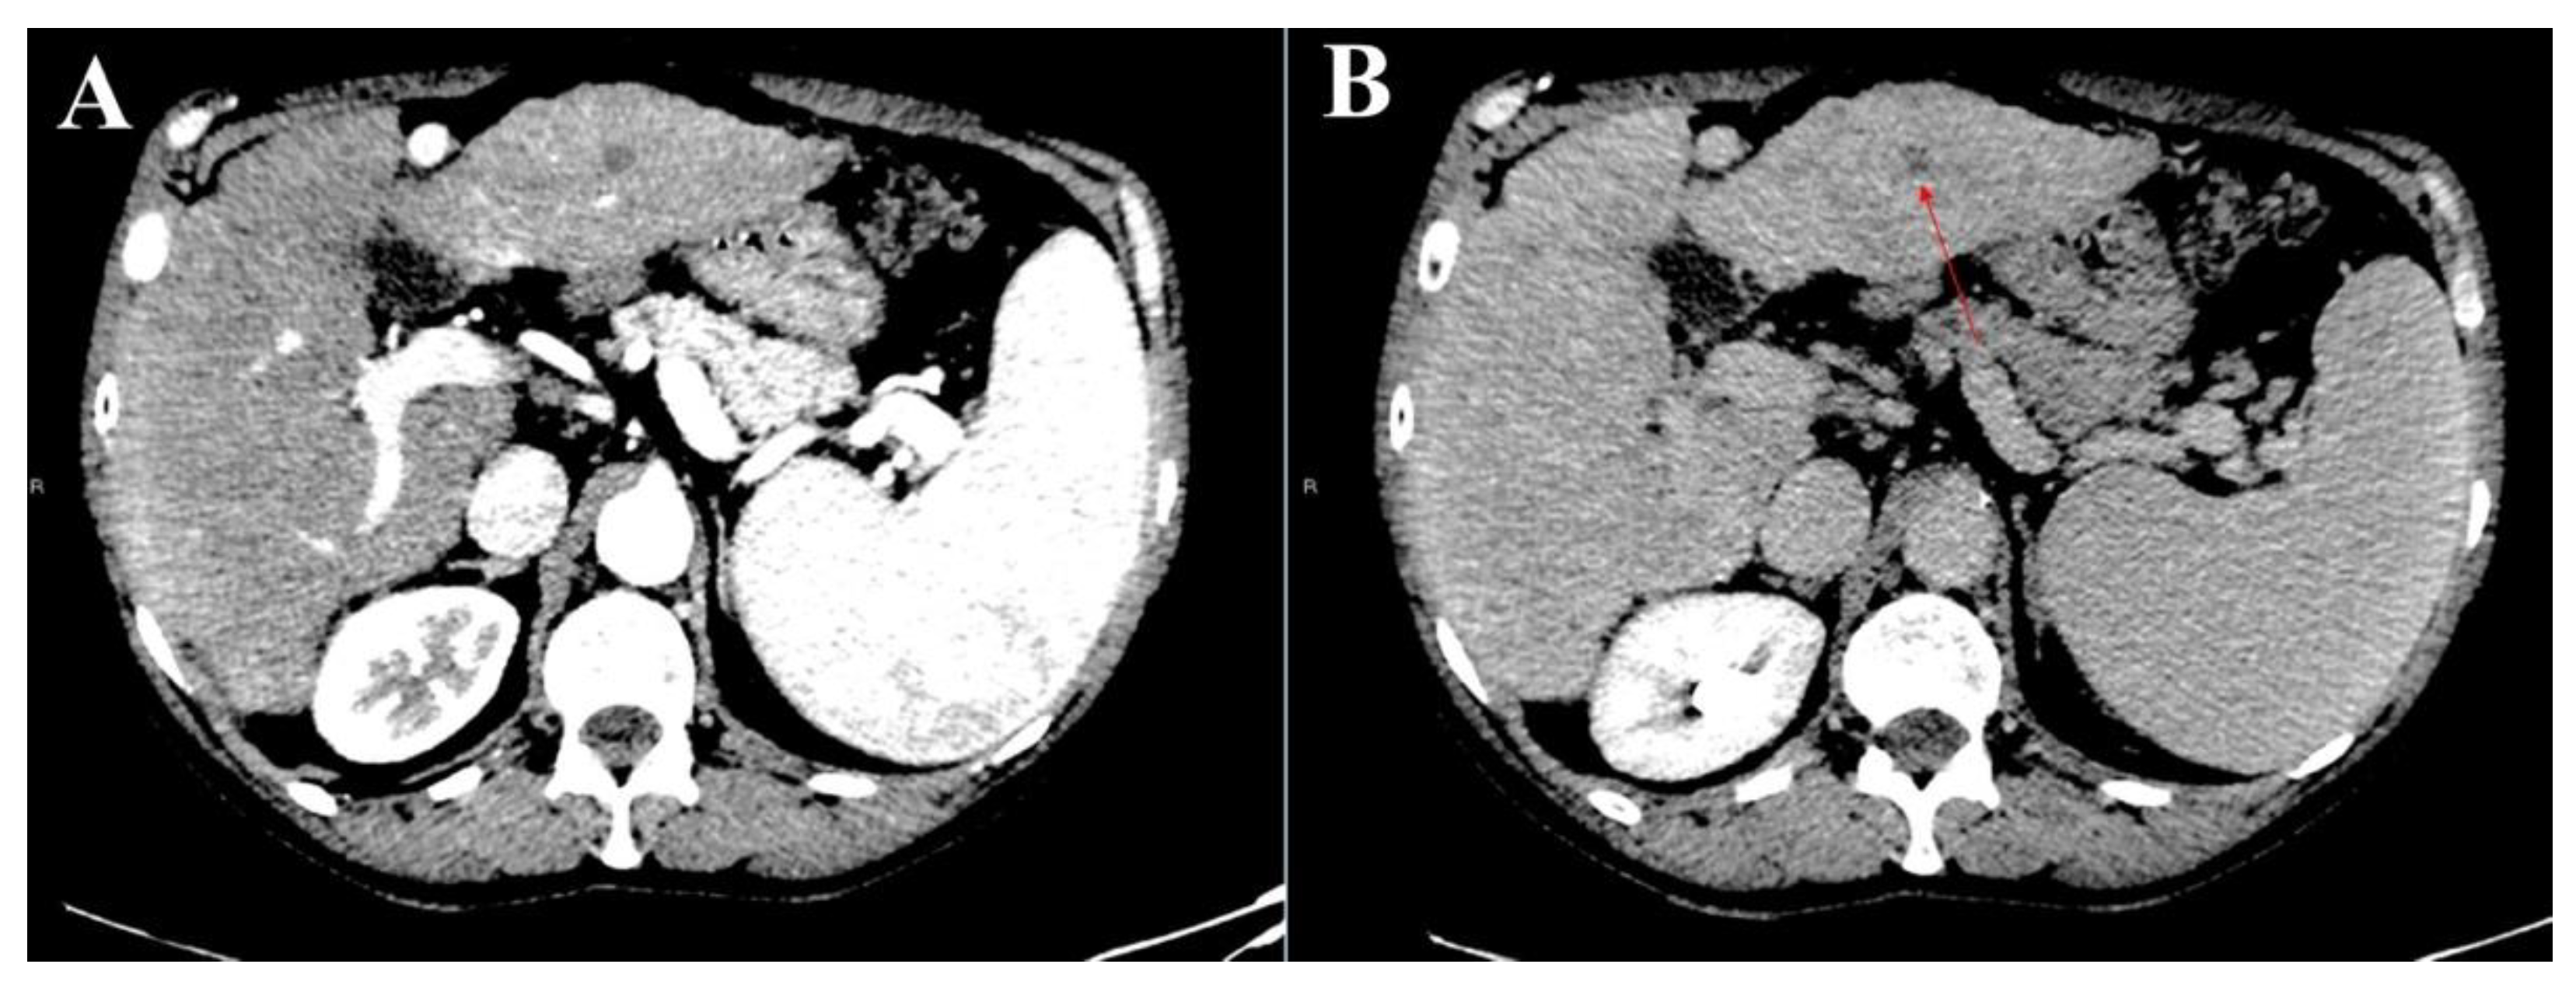

3.1. Atypical Liver Nodule Characteristics

3.2. Feasibility of Liver Biopsy

3.3. Intra- and Inter-Reader Agreements